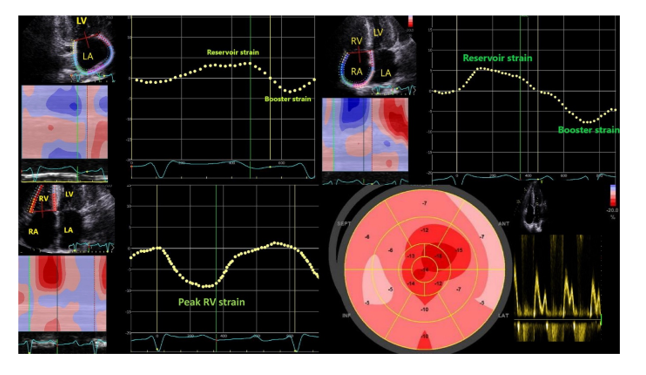

Left polar map of peak systolic longitudinal strain obtained from a Takotsubo syndrome (Our patient) and right polar map of typical anterior ST-segment elevation myocardial infarction patient (for comparison to our patient).

His CAG was done which revealed non-critical CAD.His Troponin and CPKMB were raised. He was diagnosed and managed as a case of Takotsubo CMP.

B) A 71-year-old man presented with progressive and profound fatigue, weight loss and palpitation. His past medical history was notable for bilateral carpal tunnel syndrome 10 years earlier. Electrocardiogram showed low voltage in the limb leads, poor R wave progression and atrial fibrillation. The echocardiogram showed a severely increased wall thickness.

Although ejection fraction (EF) was preserved, longitudinal function by tissue Doppler was markedly reduced. As shown in the image below, the longitudinal strain demonstrated a distinctive apical sparing pattern.

The sum of apical segmental strain values was greater than the sum of mid and basal segmental strain values in the “bull’s eye” strain plot (image below), a finding that has been shown to be sensitive and specific for cardiac amyloidosis.

Figure: Bulls plot showing classical cherry on top pattern with speckle tracking imaging on RV

The patient will need a technetium pyrophosphate cardiac scan with SPECT CT, which will confirm the diagnosis. Genetic testing will be done after confirming to point out specific mutations.